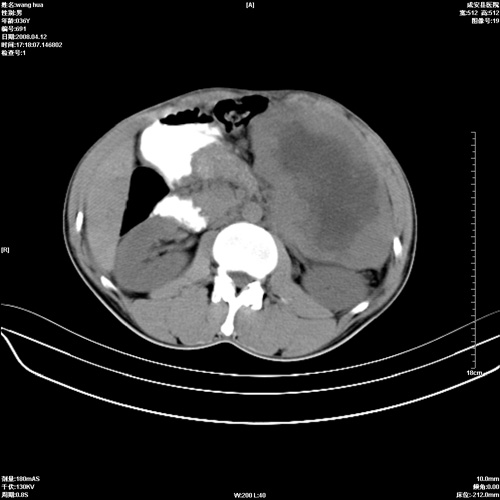

标题: CT12809:男36岁,自感上腹胀5天,B超诊断为脾肾之间占位,血 [打印本页]

标题: CT12809:男36岁,自感上腹胀5天,B超诊断为脾肾之间占位,血

请各位老师先分析一下定位 明天做增强

确实需要强化!先大胆预测一下,来源于脾脏的占位,血管瘤或淋巴瘤可能性大。

脾脏肿瘤,有钙化,增强再说

脾脏明显增大,其内见巨大低密度灶,境界不清,病史较短,考虑恶性病变脾血管内皮细胞肉瘤可能。建议增强扫描与脾脏淋巴瘤及血管瘤鉴别。